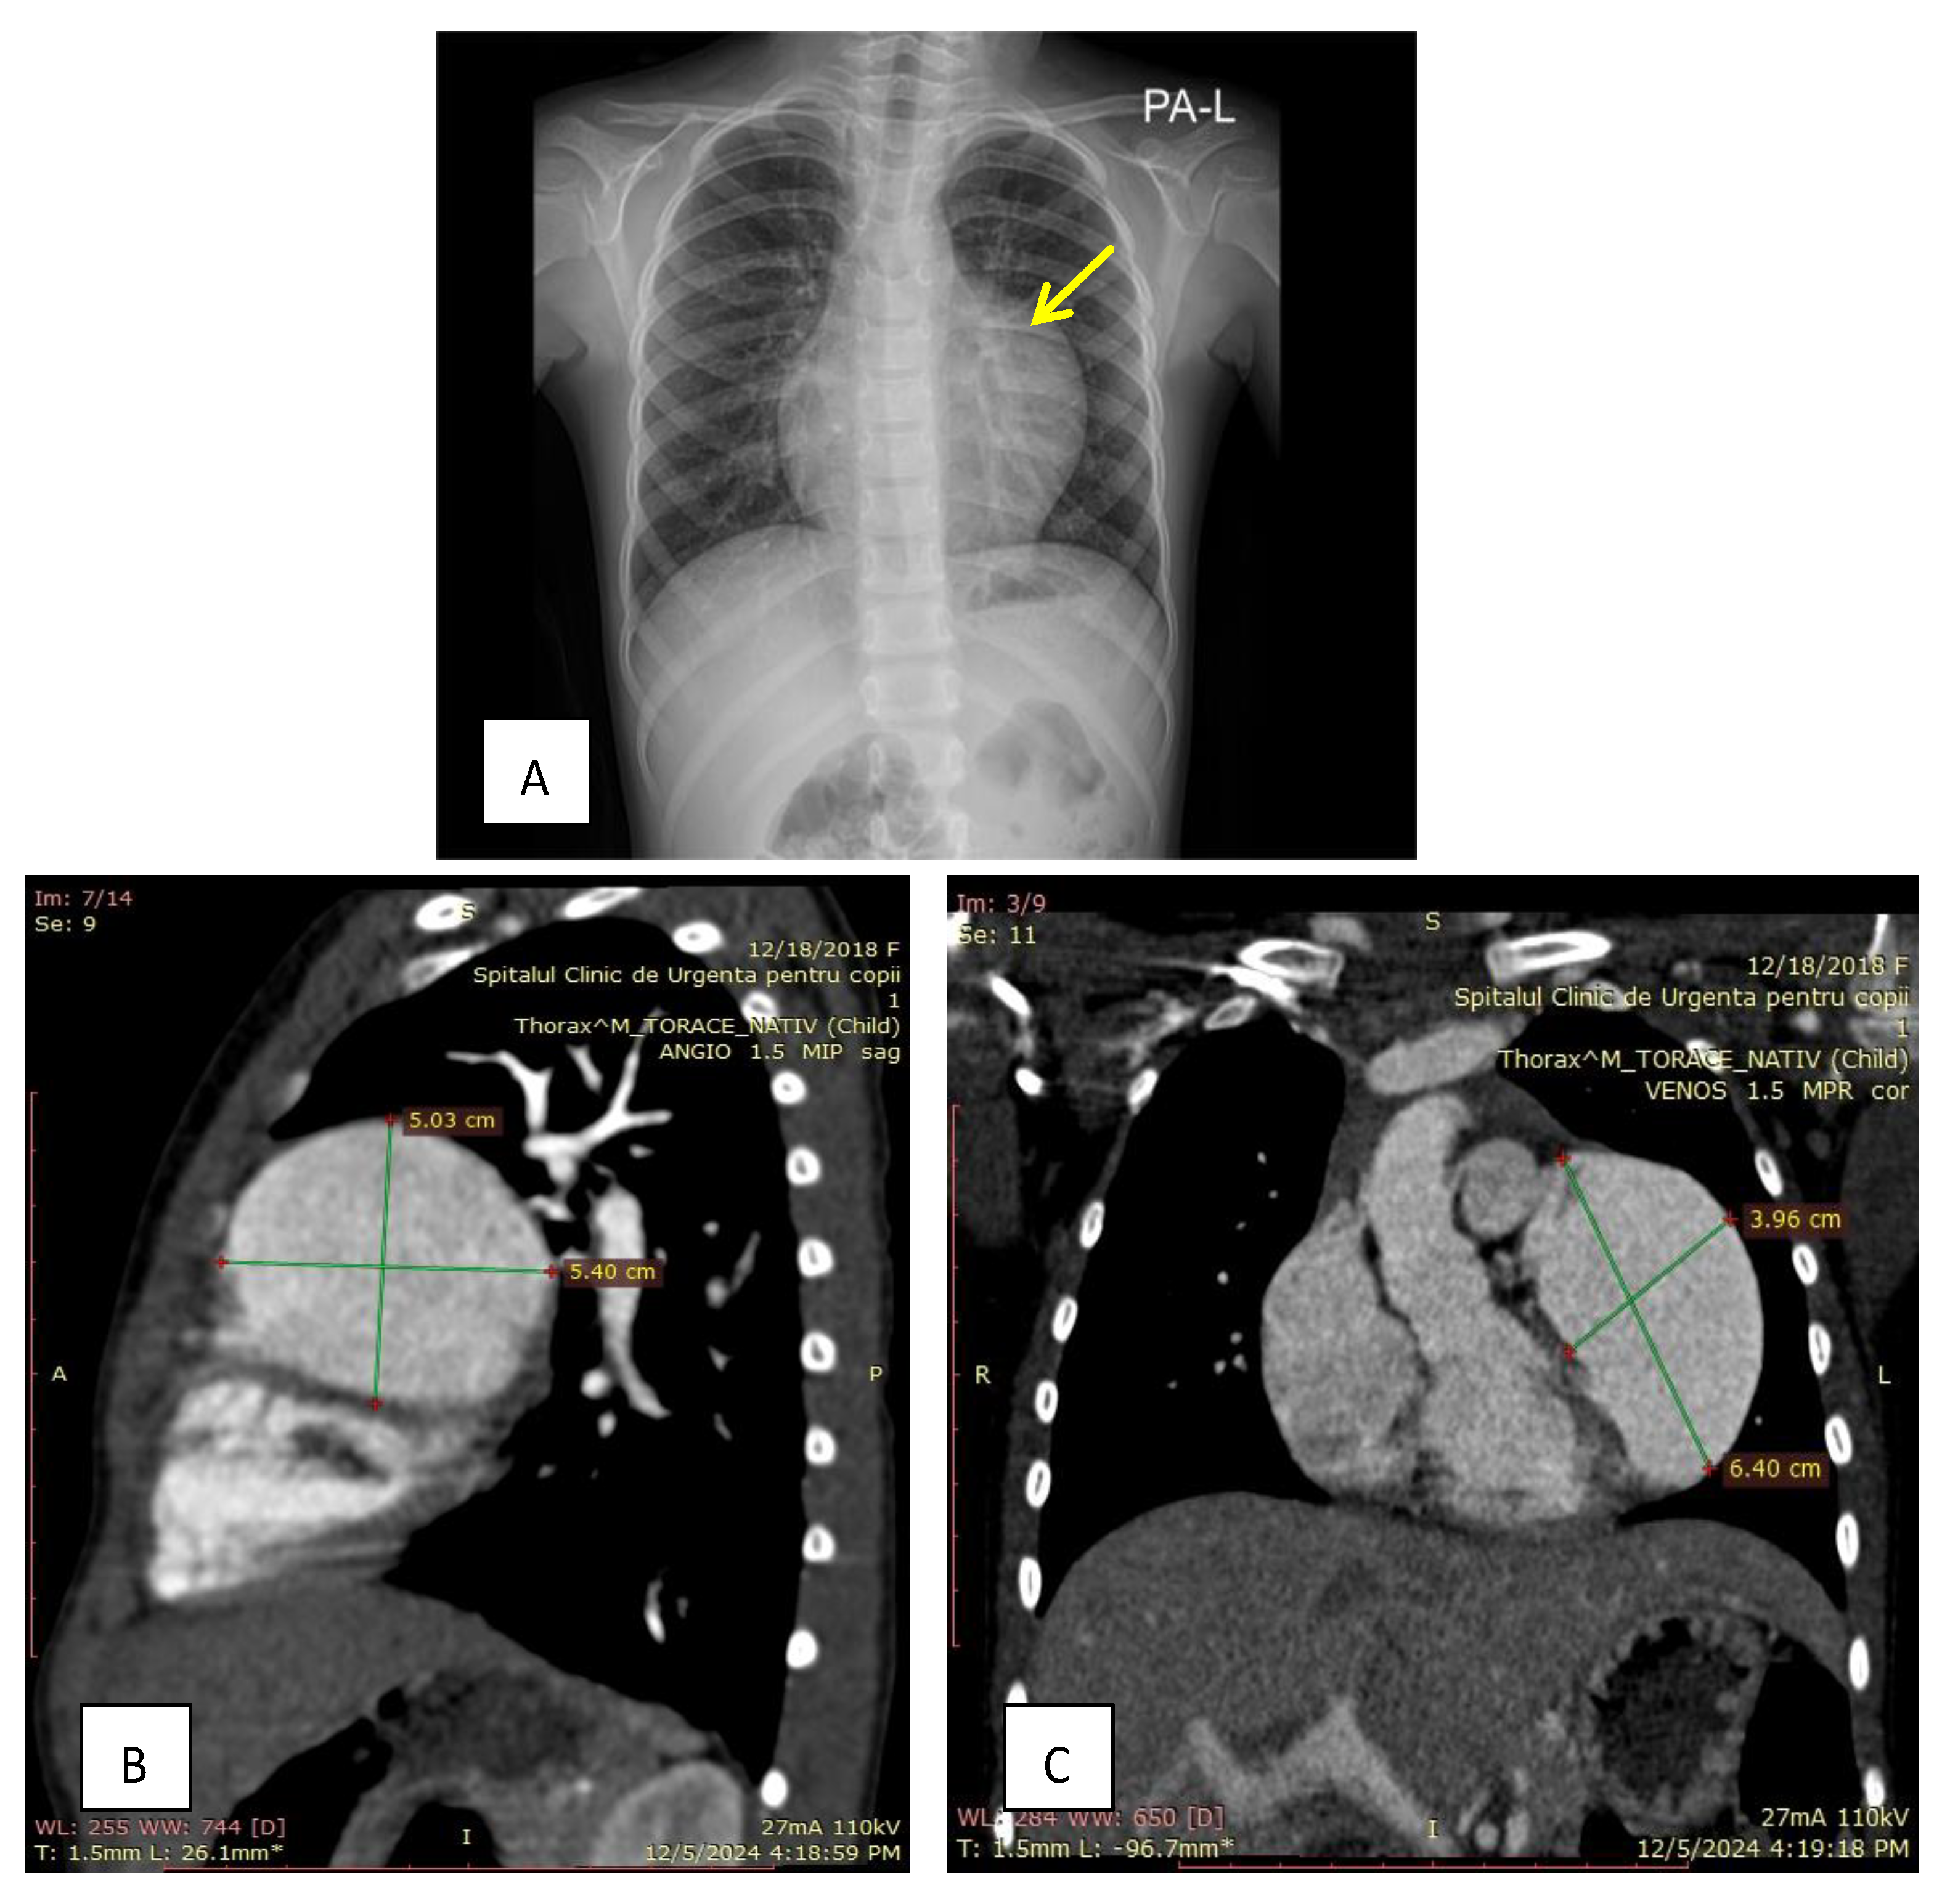

2. Case Presentation